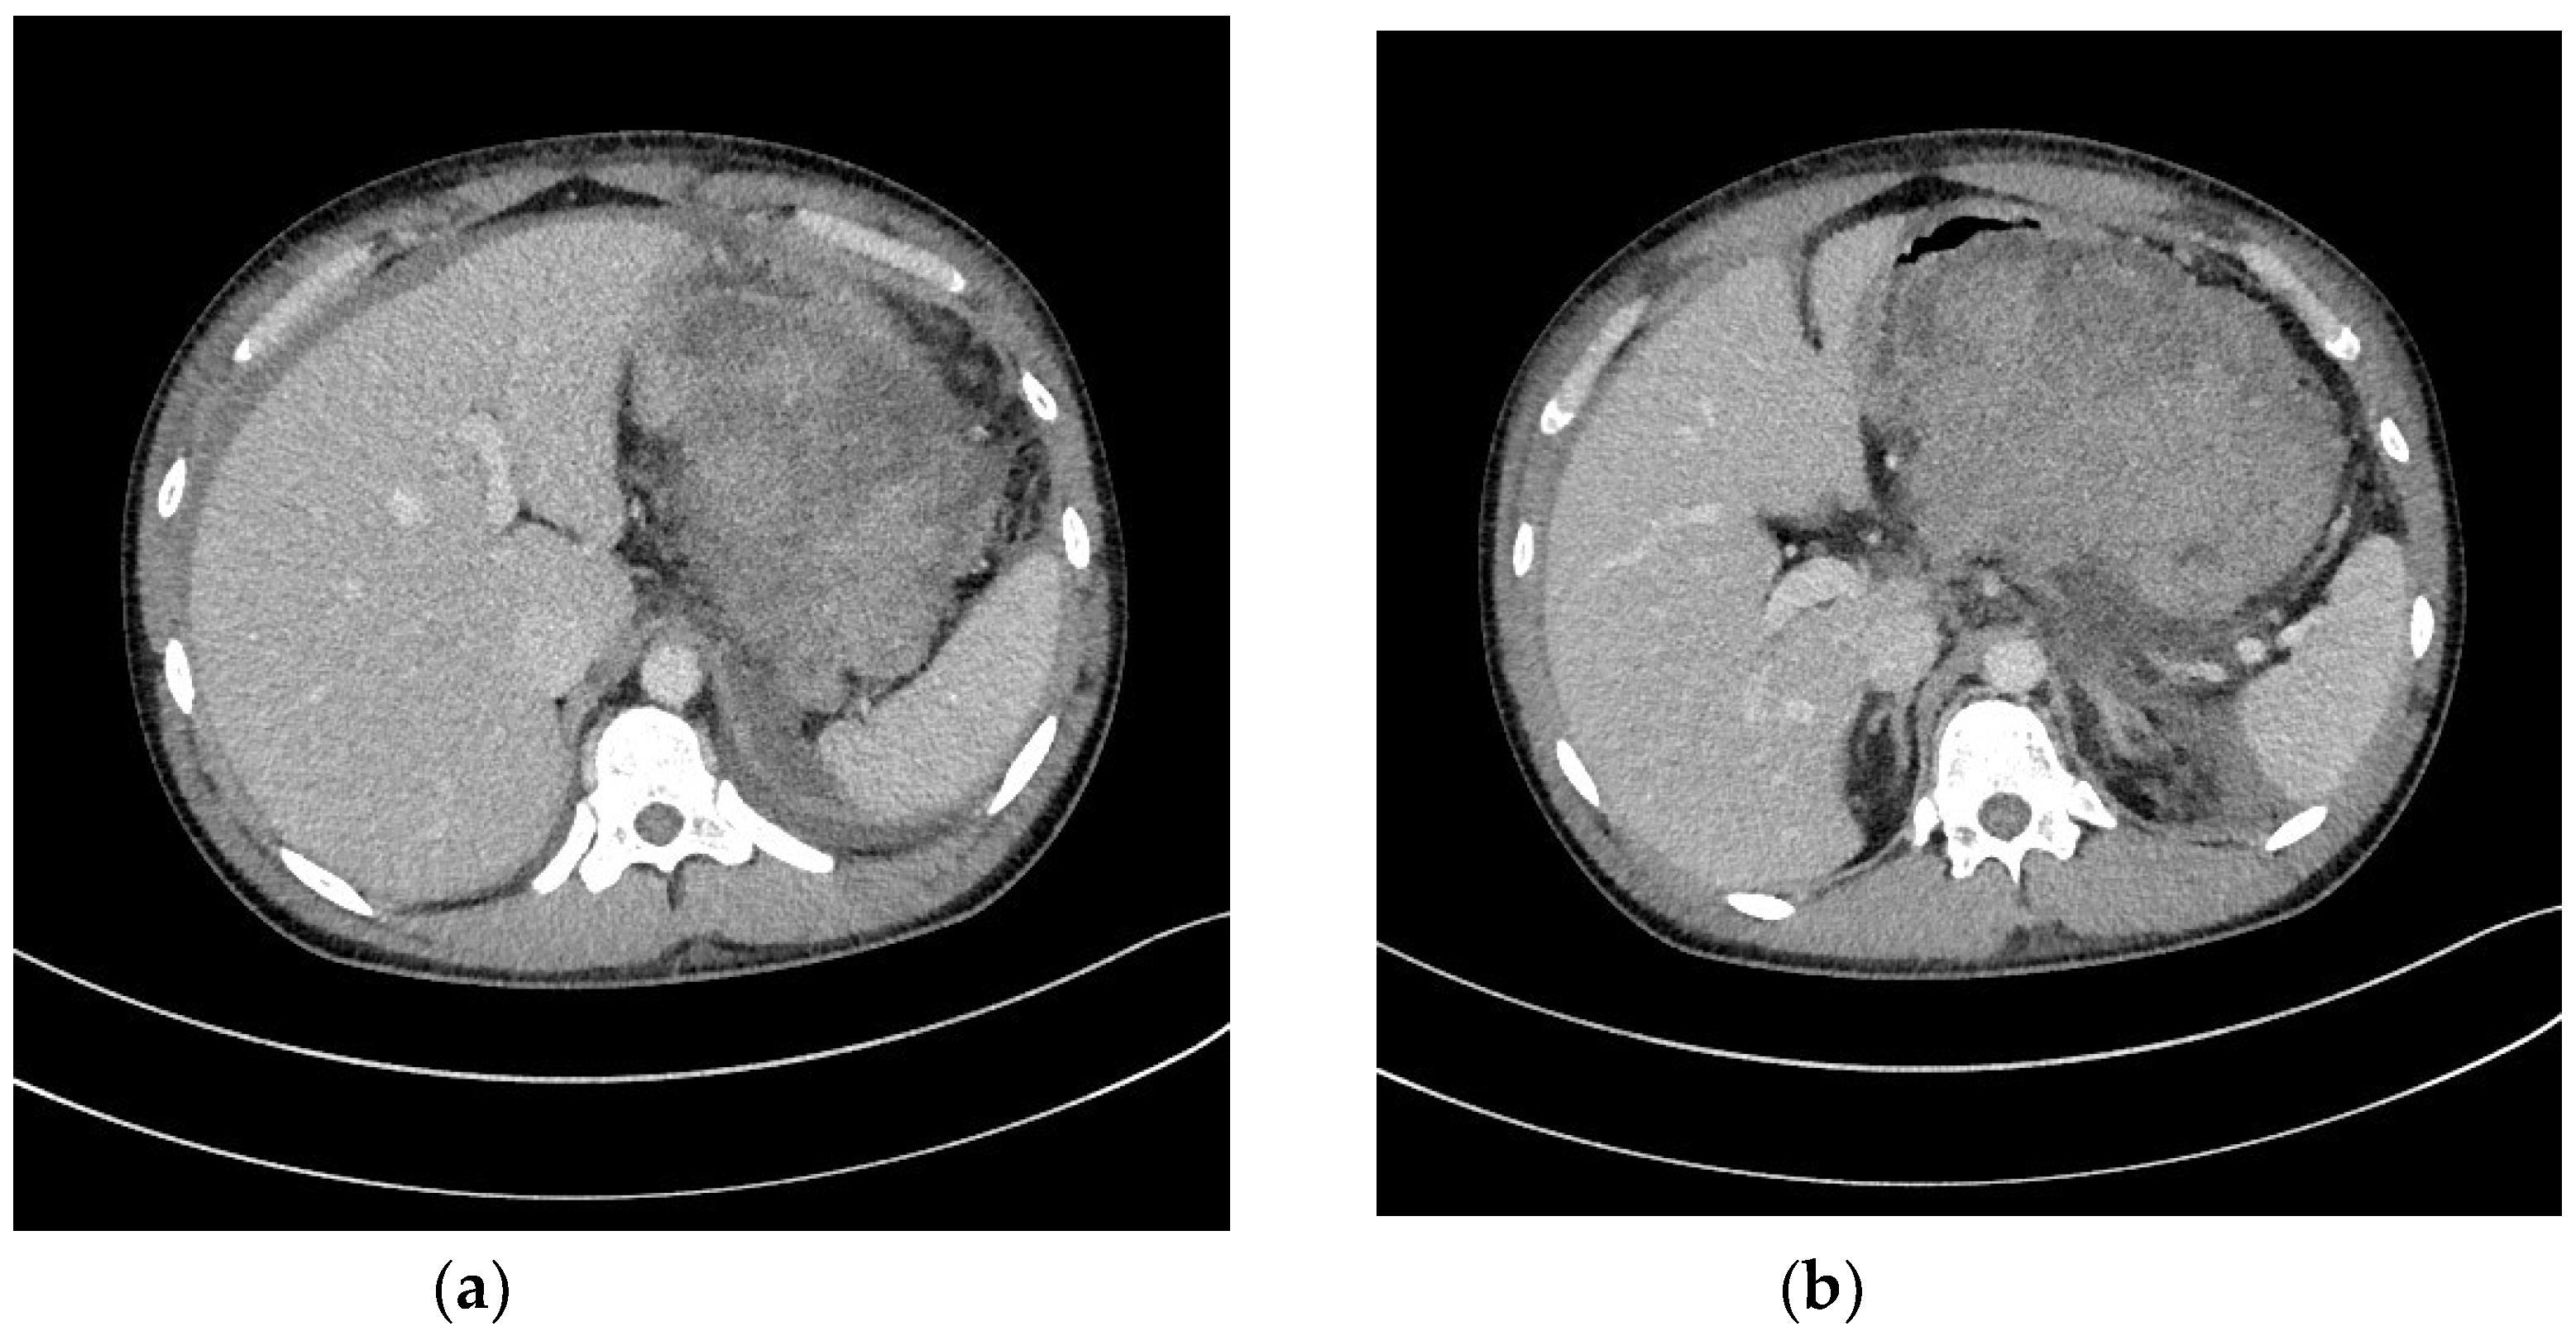

2. Strategy of Interventional Treatment

3. Transmural Endoscopic Drainage